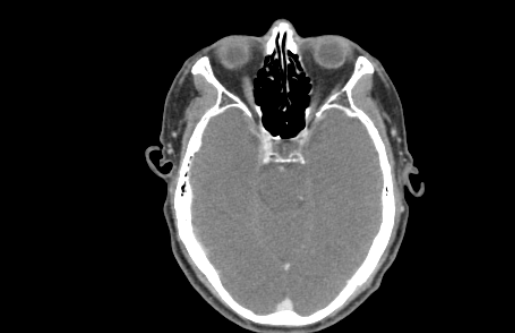

CTA MRI Brain

MRI Brain X-Ray

CT Lung MRI Brain

MRI Brain